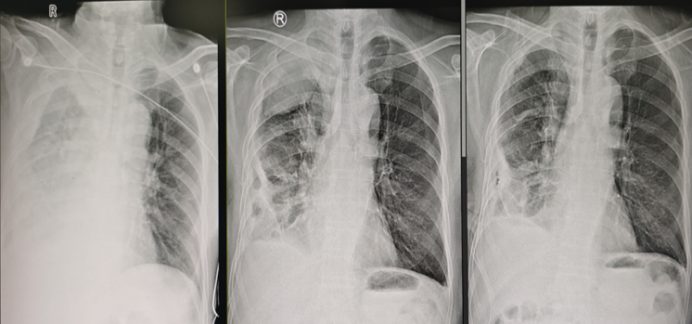

病例2:男性患者,60余岁,因肺炎伴少量胸腔积液入院,NGS检测病原体为口腔普雷沃菌。经询问病史,患者口腔卫生状况极差,且无其他基础疾病。遂予美罗培南抗厌氧菌治疗,治疗后患者体温及炎症指标快速下降。数日后,患者再次出现发热症状。胸片示大量胸腔积液,且已进展为脓胸。随即为患者放置胸管引流,之后患者体温再次下降。过程中给予尿激酶胸腔内注射,后因血尿停用。几天后患者体温再次升高,复查胸片可见右上肺出现包裹性积液(图3)。请CT室医师协助,从肩胛骨内侧另置一根胸管进行引流,然而患者病情仍未得到改善,持续发热,因此决定实施内科胸腔镜下粘连分离术。

图片

3  入院后患者胸片变化

该患者胸腔内存在大量粘连带及脓苔,若仅依靠胸腔镜或活检钳进行钝性分离,操作效率极低,难以有效清除脓苔。而在胸腔镜下采用冷冻治疗,效率会显著提高。但该操作存在一定风险,术中需格外谨慎。由于胸膜腔感染的患者胸腔正常结构消失、粘连对于镜下视野干扰较大,红色区域究竟是胸壁还是肺组织,需要仔细辨别。若粘连与肺组织结合极为紧密,切勿强行分离,否则可能撕裂肺组织,引发大出血;此外,还可能导致持续性漏气,使气胸难以愈合。该患者内科胸腔镜术后状态明显改善4,未再发热,顺利出院。

4  患者内科胸腔镜治疗前后对比